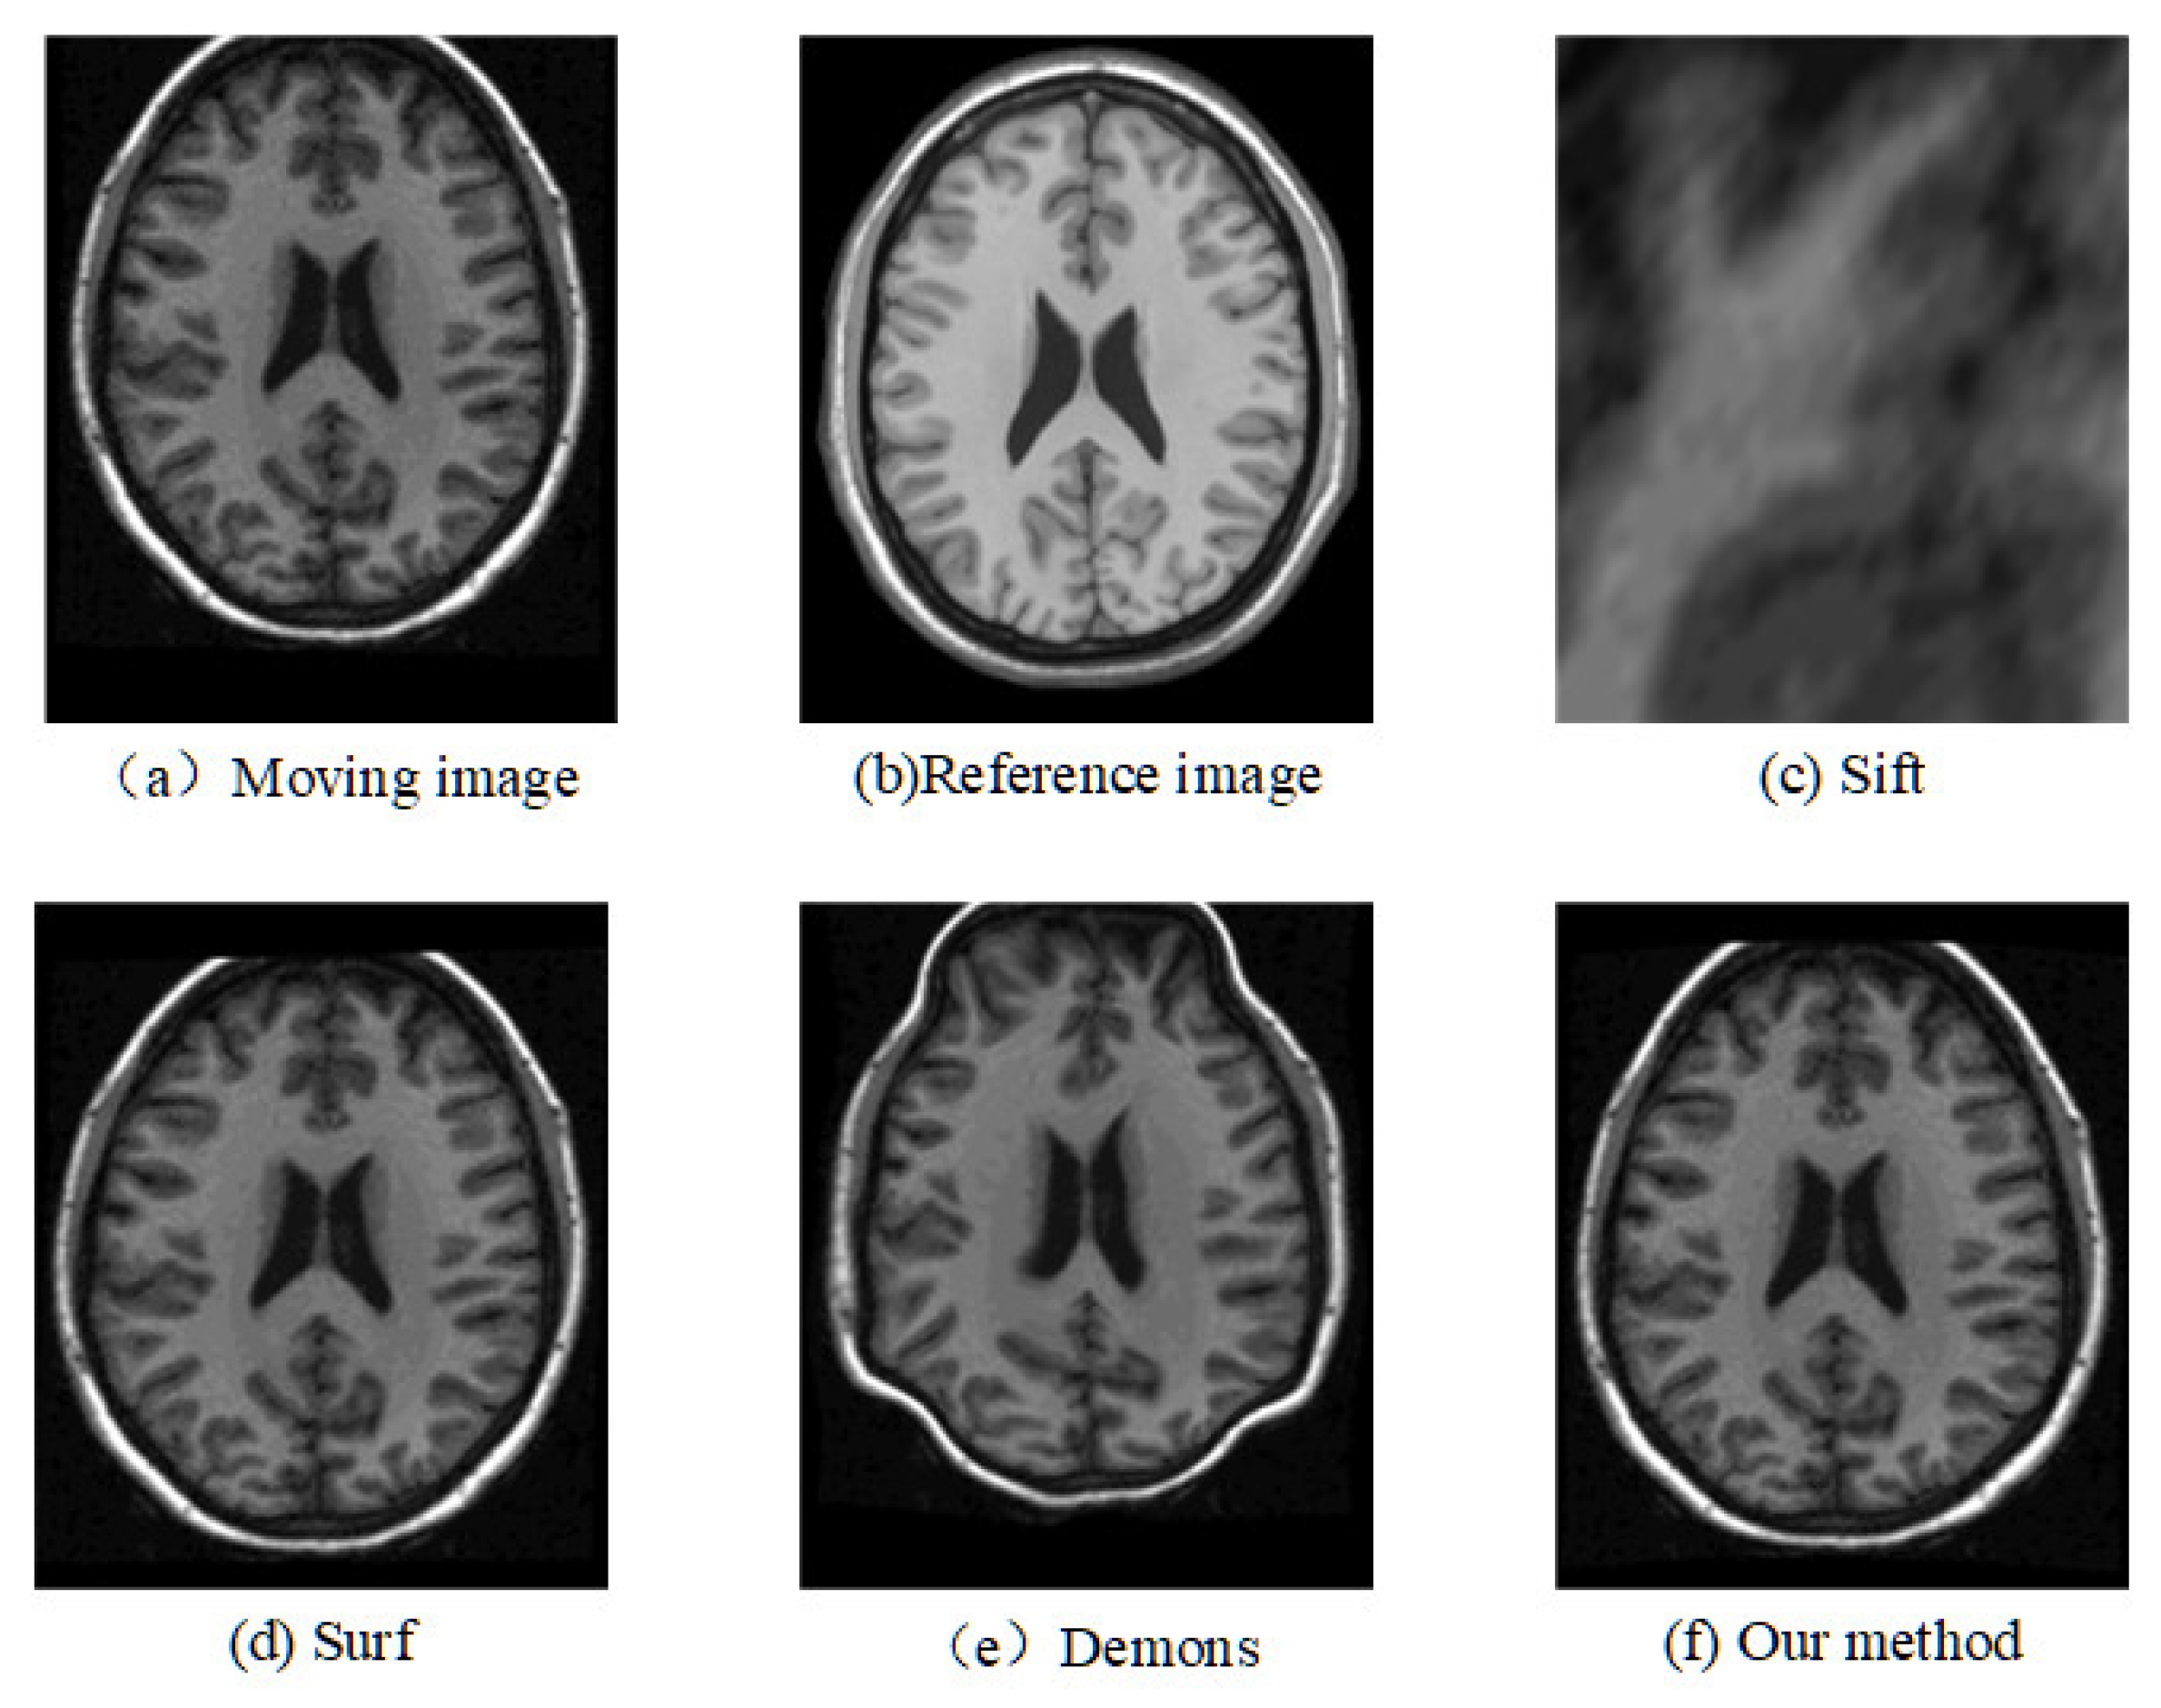

The registration results of the two datasets are shown in Table 1 and Table 2. Moreover, we randomly select two slices based on CUMC12, shown in Figure 6 and Figure 7, and those based on MGH10, shown in Figure 8 and Figure 9.

The corresponding relationship of spatial location can be seen in Figure 6 to Figure 9 between moving image and the reference image. These figures show lots of differences between the moving image and the reference image, including the significant shift of location, different size, the respective concavity and convexity of cerebral cortex, and different degree of smoothness. After registration, the results of our method are the closest to the reference image in multiple aspects, such as spatial location, image size, and brain contour. Surf is second-best, and close to the reference image for the spatial location and size. However, it represented the distortion in the contour of the cerebral cortex to some extent (as shown in Figure 6), and the skewing for some slices (as shown in Figure 8) after registration. The results of the Demons are totally different from the reference image in the spatial location, image size, and contour of the cerebral cortex. It also showed great distortion and deformation. Sift is the worst algorithm, and its current result did not show the brain shape.

Figure 6. Registration results of any one slice from any T1 image based on CUMC12 dataset.